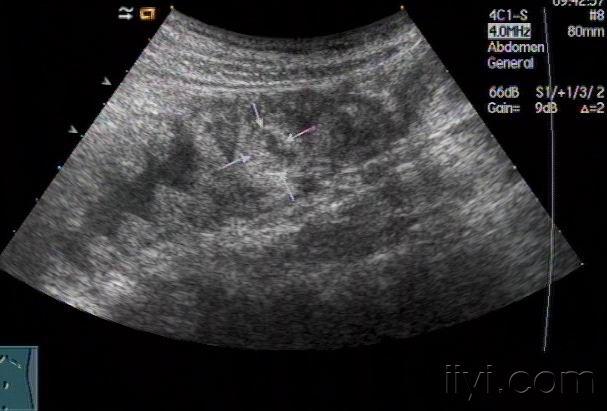

右下回盲部混合性包块,是否阑尾脓肿?

图片尺寸640x512